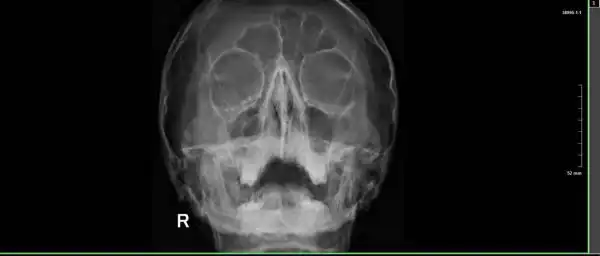

Лица вэйперов после взрыва электронной сигареты

Любители электронных сигарет считают вэйпы безопасной альтернативой курению. Но если взглянуть на лица вэйперов, пострадавших от взрыва аккумулятора сигареты в момент затяжки, то в этом возникают сильные сомнения.